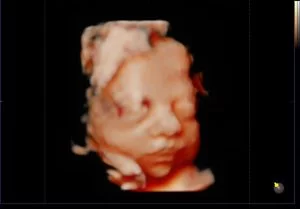

Como são as imagens vistas no exame?

Aqui está um exemplo de como será a visualização do bebê durante o exame: